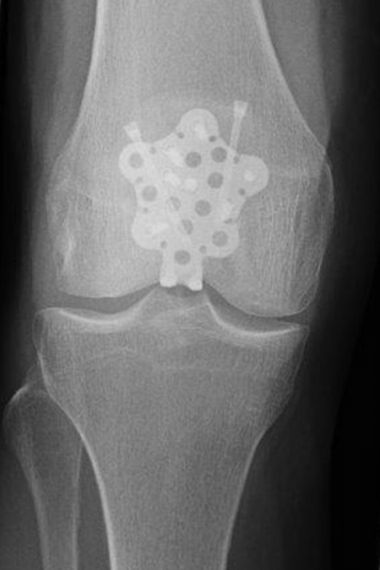

BRÜCHE UM DAS KNIEGELENK

Bild Starplatte Ergebnis Patientin zeigt ihre Narbe am Knie

Ich bin auf das rechte Knie gefallen und konnte gar nicht mehr laufen. Die Kniescheibe war gebrochen und wie man in den Röntgenbildern gesehen hat, gleich in viele Teile. Ich bin in der Rosenhöhe gut operiert worden. Ich kann heute wieder alles machen und komme auch auf der Treppe ohne Probleme zurecht.

Mehrfragmentärer Kniescheibenbruch nach Sturz, der intraoperativ insbesondere neben quer verlaufenden Brüchen, auch horizontale Bruchkomponenten umfasste. Versorgung mit einer speziellen winkelstabilen Platte. Das Ergebnis zeigt eine sehr gute Funktion mit Wiederherstellung der vollständigen Kniegelenksfunktion.